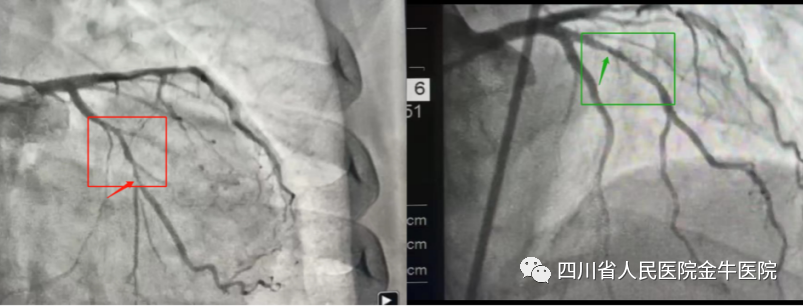

近日,林婆婆因“反复胸痛伴气促2+月”入住我院心内科。接诊后,患者冠状动脉造影提示:冠状动脉存在多处狭窄,最严重处约90%,明确诊断冠状动脉粥样硬化性心脏病。 经副院长、心内科副主任医师翁一文统筹安排,我院心内科介入团队,在省医院心内科副主任医师韩虎魁的指导下,在患者冠状动脉严重狭窄处置入药物洗脱支架一枚,成功完成我院首例经皮冠状动脉介入术。 术后,主管医师密切关注林婆婆病情动态,实时对症支持治疗,在心内科医护团队的精心照顾下,林婆婆恢复情况非常好,各项指标趋于正常,深得患者和家属的好评! 经皮冠脉介入术翻开了心内科崭新的一页,为我院胸痛中心的建设奠定了基础,是我院建设具有三甲综合医院实力的区域性医疗中心的有力助力。